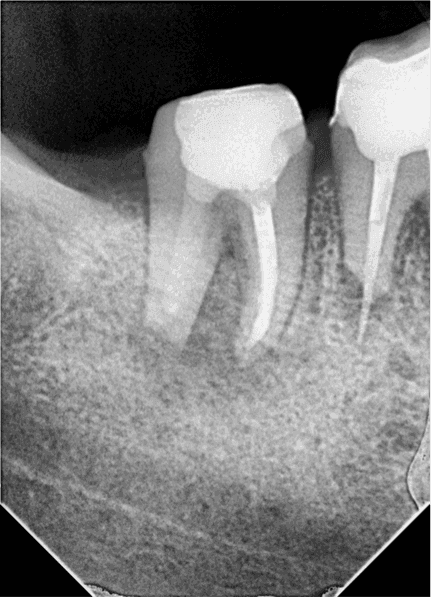

3. seansa başlamadan aldığımız rvg de kırık eğenin mesial kök ucuna daha yakın olduğu tespit edildi. (RESİM 9). Mesial kanaldan serum irrigasyonu yaparak serumun distal kanaldan drene olması ve eğenin tekrar distal kökucuna taşınması planlandı. Plan işe yaradı kırık eğe distal apikal açıklıkta izlendi. (RESİM 10)

RESİM 9: Apikal bölgede hareket eden kırık eğe